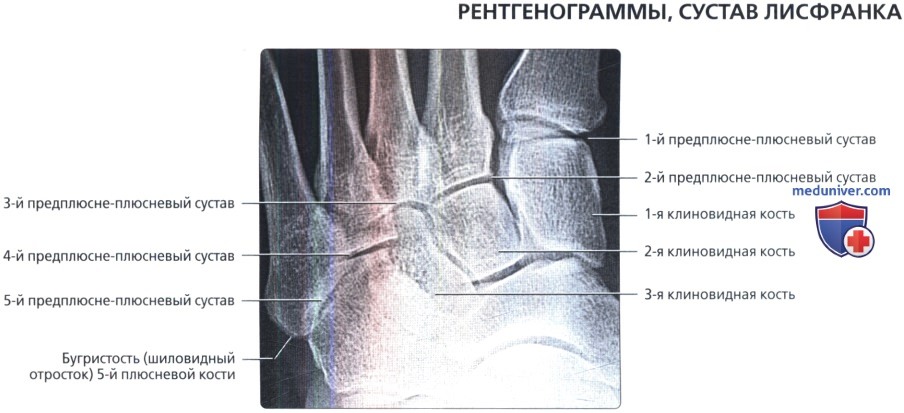

Анатомия суставов Шапарова и Лисфранка: фото и информация